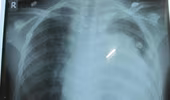

ANTĐ - Trong nhiều triệu chứng của các căn bệnh nguy hiểm thì đau ngực được nhiều người quan tâm nhất. Triệu chứng này cũng có thể cảnh báo tình trạng bệnh tật nguy hiểm đến tính mạng chính là nhồi máu cơ tim cấp tính. Tuy nhiên, trong thực tế chúng ta cần phân biệt những dấu hiệu của các triệu chứng không phải là nhồi máu cơ tim, nhưng các căn bệnh này cũng gây ra nguy hiểm không kém.

(ANTĐ) - Không như dự kiến ban đầu, hiện vẫn còn một nạn nhân trong vụ cháy tòa tháp đôi của Tập đoàn Điện lực Việt Nam (EVN) chưa thể xuất viện do bỏng hô hấp với nhiều triệu chứng ho, khạc đờm đen, đau ngực, khó thở.

ANTĐ - Ợ nóng được coi là dấu hiệu thông thường của bệnh trào ngược dạ dày thực quản (GERD) nhưng cũng có những căn bệnh gây ra cảm giác nóng rát nơi ngực. Hãy tìm hiểu những loại bệnh cũng có dấu hiệu đau tức như bị ợ nóng.